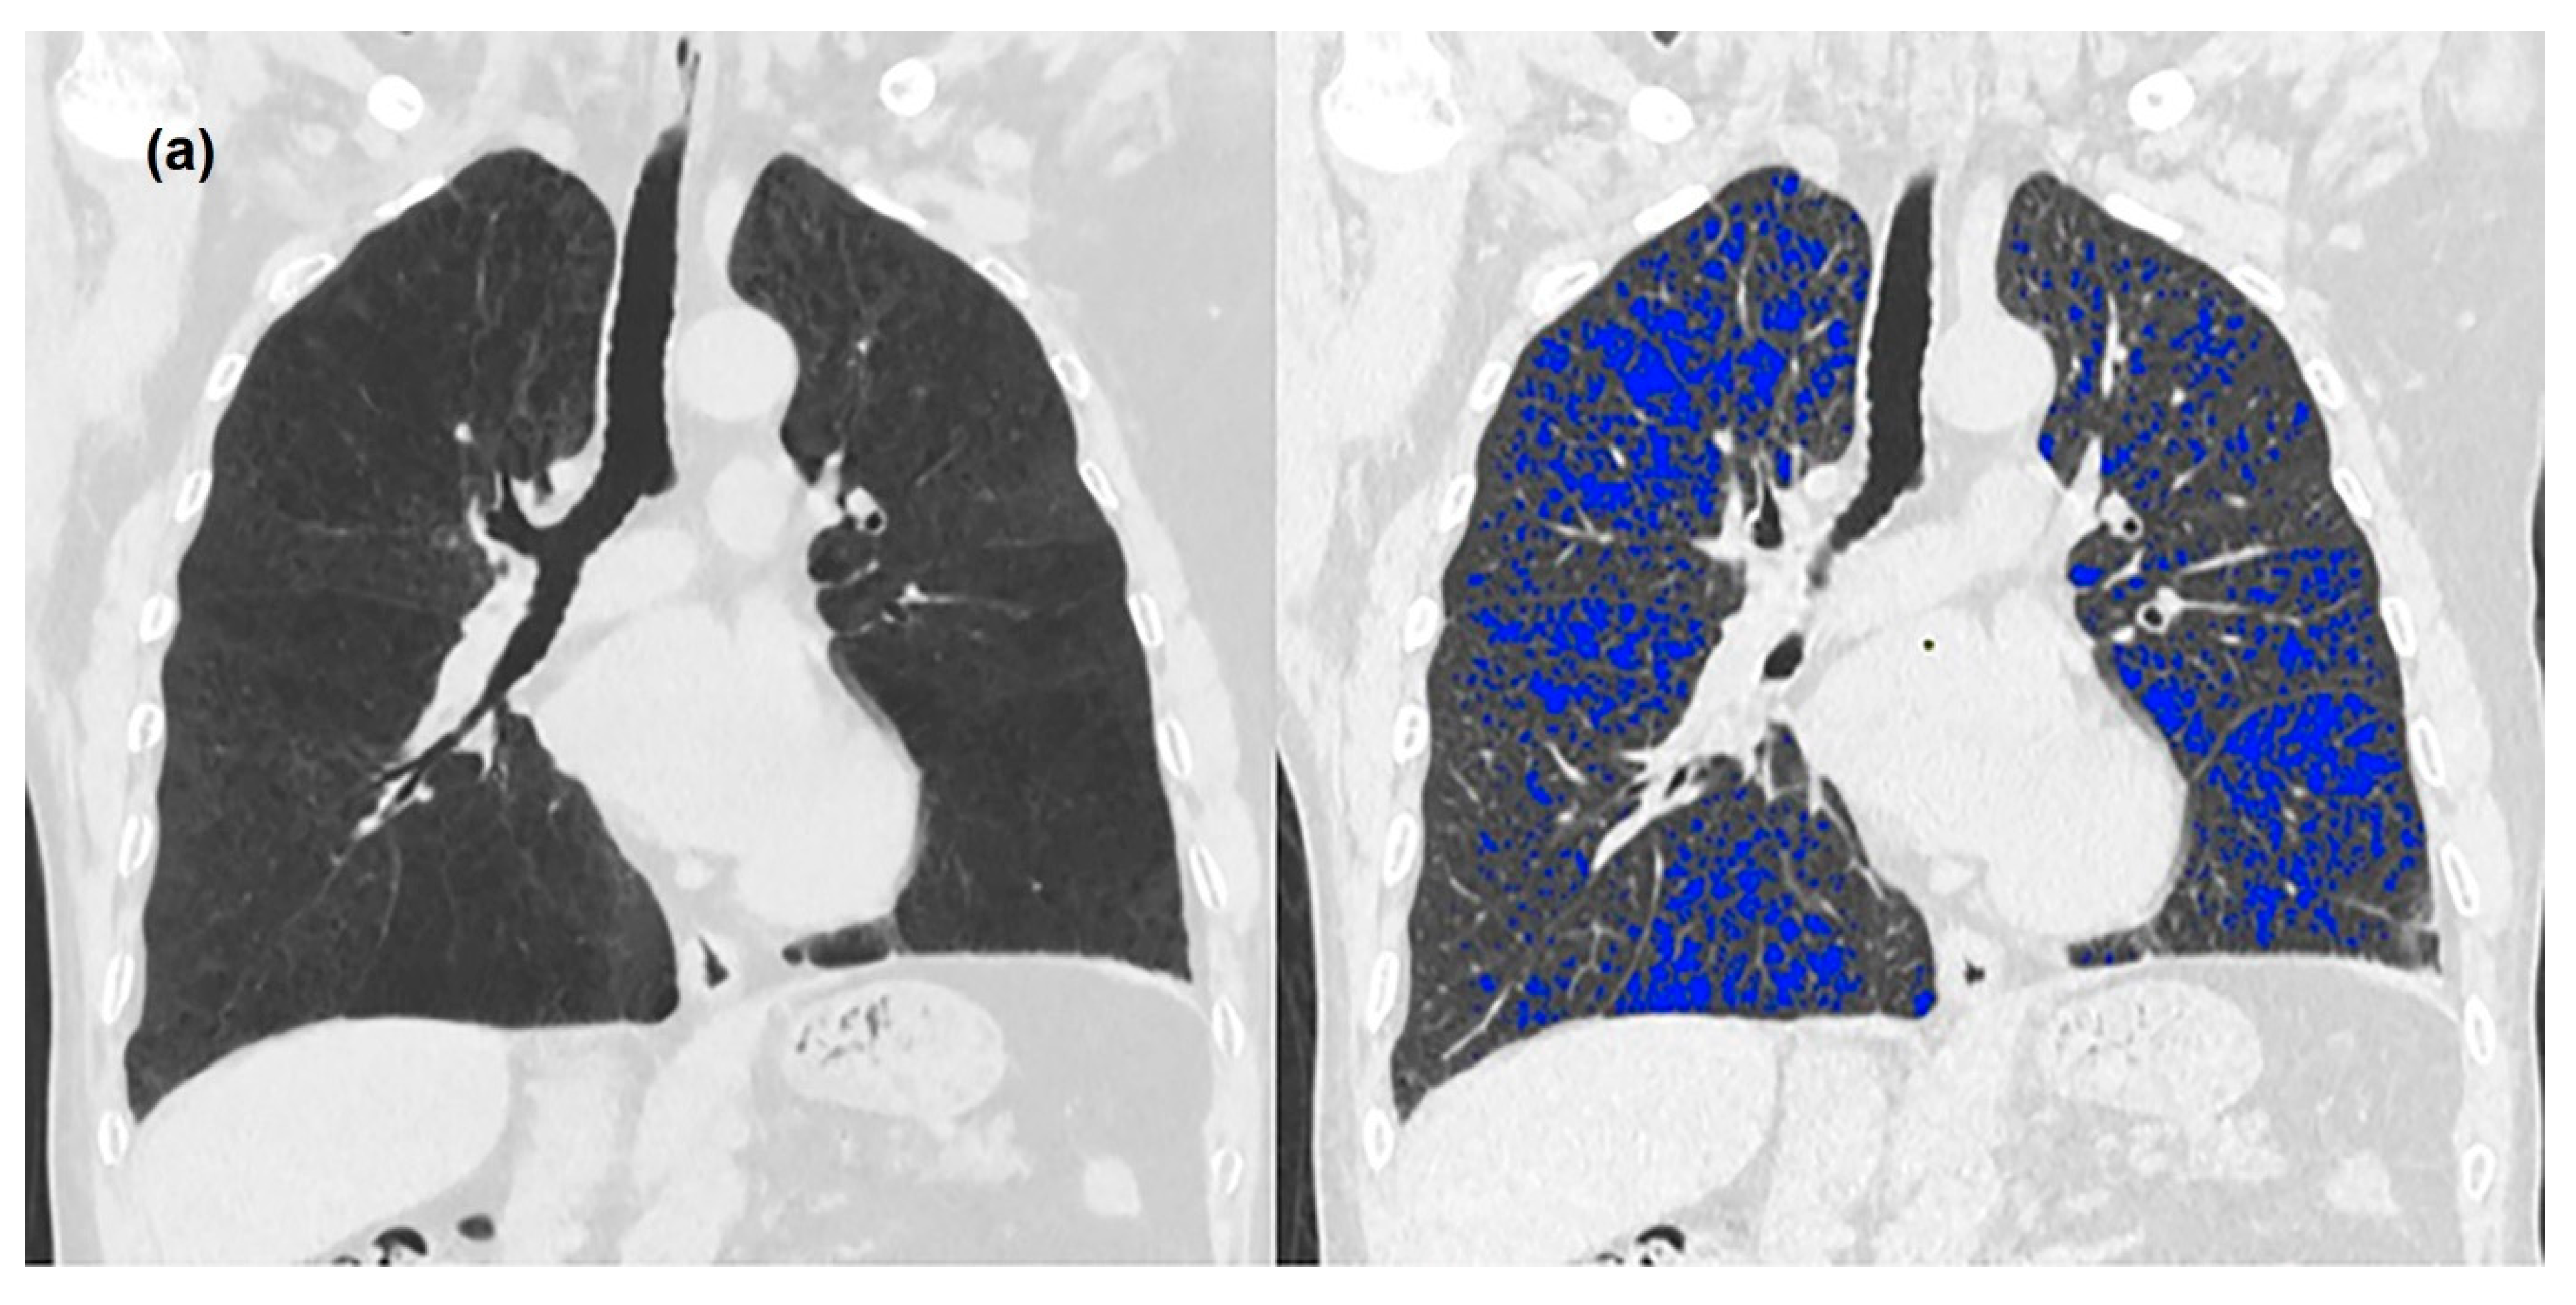

2.3. Image Analysis

3.2. Quantitative Measurements of Standard-Dose and Ultra-Low-Dose CT